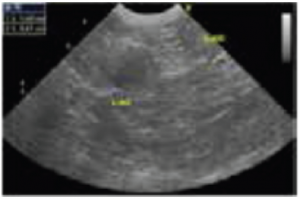

Ecografía abdominal:

Se identificó una masa en el lado craneal de la glándula suprarrenal izquierda (Figura 1).

Figura 1

Sobre la base de los resultados obtenidos a partir de la estimulación con ACTH y la ecografía abdominal, se diagnosticó hipercortisolemia debido al tumor en el lado craneal de la glándula suprarrenal izquierda. Aunque se le recomendó al propietario proceder a la extracción del tumor, no se recibió su consentimiento debido a la edad del perro. Por lo tanto, se aumentó la dosis del trilostano como un método de tratamiento médico. Como resultado de este tratamiento, el nivel de ALT disminuyó y se estabilizó posteriormente.